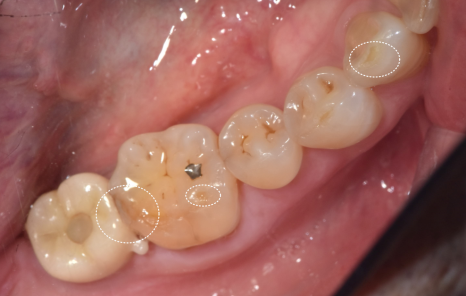

240605

치아를 보는 순간 알 수 있었던 사실 하나는

"아, 이분 딱딱한 음식 좋아하시는구나."였습니다.

위아래 치아의 씹는 면이 전반적으로 다 닳아있었거든요.

특히 문제는 금이 간 앞니였습니다.